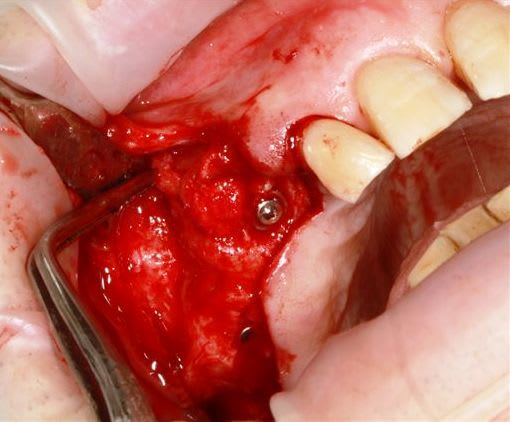

13 fenestration vestibulaire j'utilise la paroi palatine, lame N°15, spreader, expansion et pose d'un 40140

modelage zone 13,finitions, mise en place du bloc osseux, qui sera soigneusement impacté (pas de vis) prélèvement d'un petit bloc triangulaire pour finir la fermeture, éponges de gelatemp, sutures.